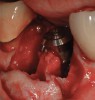

Figure 17  In another case, the mandibular left second molar was fractured and hopeless.

Figure 17